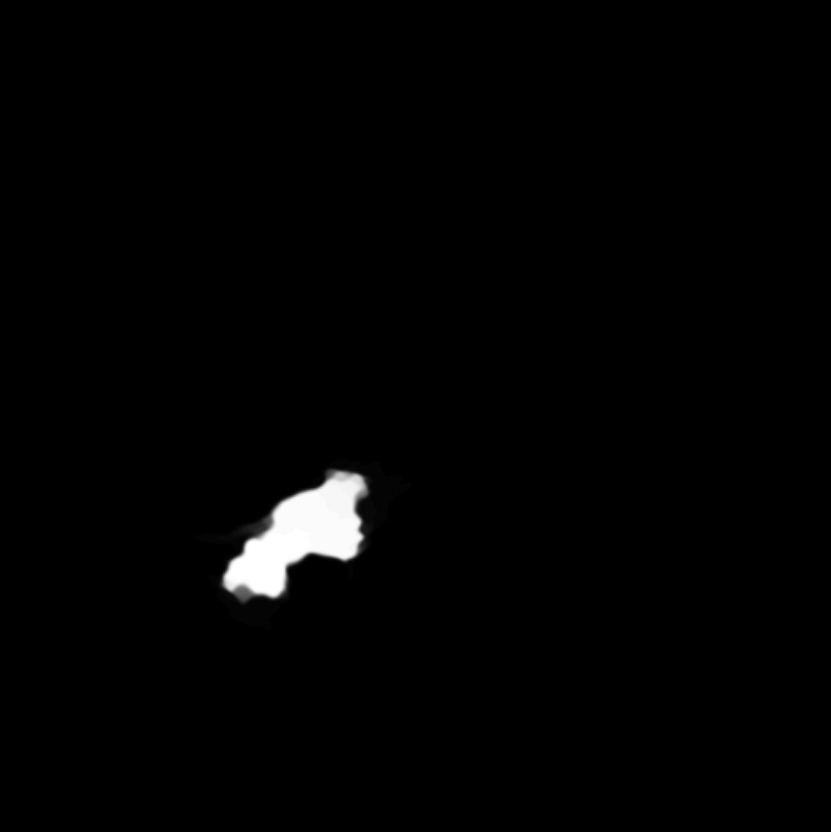

In some cases the image is so noisy, that we would like to segment the noise out of it before segmenting the image. We consider once more the MR image from Fig. 4 with of added noise (as in (15) with ), such that the borders of the tumor are heavily distorted. At the first step, we use the adaptive eigenspace to filter the image (K=150) and then we segment the tumor out of the filtered image. The segmentation is performed with much success, see on the right of Fig. 9. The segmentation is very close to the one done on the original image, without noise, shown on Fig. 4.